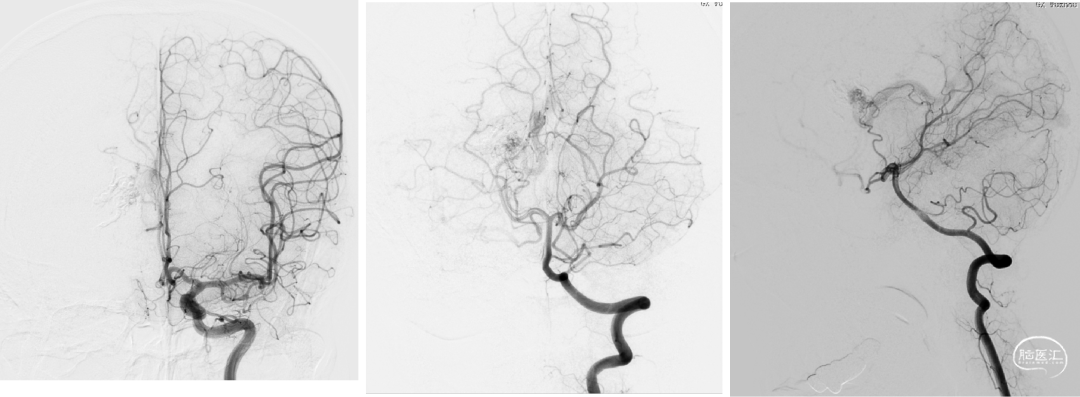

术前DSA:右侧基底节动静脉畸形,豆纹动脉供血,经大脑静脉、直窦、横窦、乙状窦引流

术前DSA

术中:超选外侧豆纹动脉(马拉松塑形),synchro10+0.008塑形,到位,15%gb,时间5min,返流拔管稍粘连。

术中:Enoyv6f双导丝到乙状窦,synchro10将apollo3cm到位;泰杰312、310x2(做塞子);控制收缩压在90以内,动脉内hyperglide4x20充盈(保护),onyx34约0.6ml(约5min),换onyx18弥散差。

术中:即刻造影脑动静脉畸形消失。